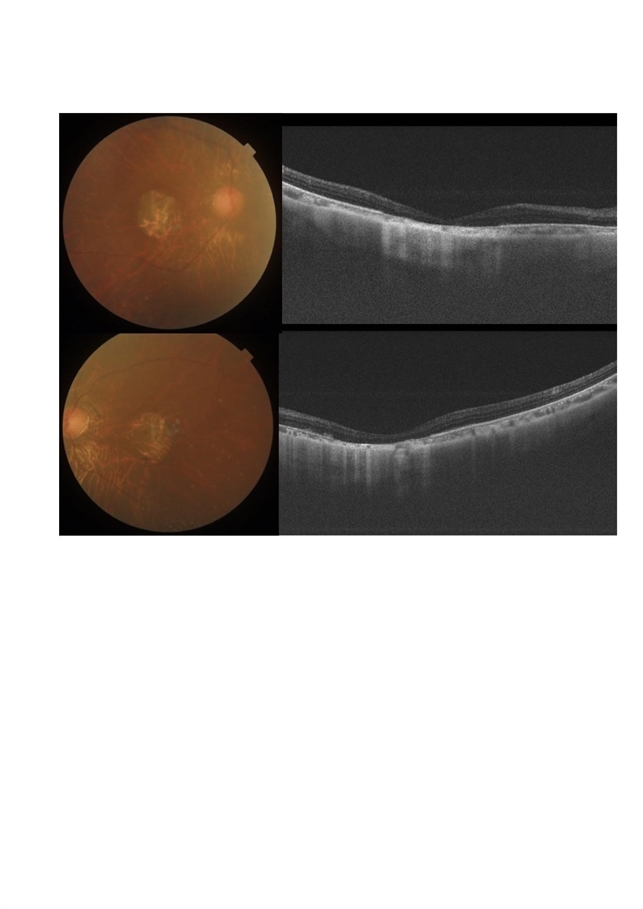

- Fundus photo of a 43-year-old female with gradual onset diminution of vision in both eyes since 2-3 years. BCVA in OU was 3/60. She was diagnosed to have central areolar choroidal dystrophy(CACD). Central areolar choroidal dystrophy (CACD) is a rare inherited disease, which causes progressive profound loss of vision in patients during their fourth decade. It is characterized by atrophy of retinal pigment epithelium, photoreceptors and choriocapillaris. IT is a progressive macular dystrophy characterized by subtle, mottled depigmentation in the posterior pole in the early stages. The depigmentation area gradually enlarges until an oval or round surface of atrophy of the retinal pigmentary epithelium and choriocapillaris is formed. Drusen or flecks are absent in a typical presentation.